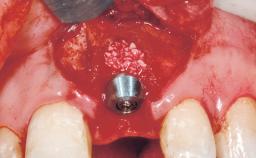

Immediate Flapless Placement of an Implant in a Maxillary Left Central Incisor Site

A 42-year-old female patient was referred to our clinic at the School of Dentistry of the University of São Paulo in November 2004, presenting a deficient restoration in the upper left central incisor. The clinical examination revealed no gingival retraction or any signs of gingival inflammation and, therefore, previous periodontal treatment was not considered. The patient presented a high lip line at full smile and a thin tissue biotype. This combination characterized a high-risk situation from an anatomic point of view, which required careful preoperative planning and cautious surgical execution.

Placement Protocol Immediate implant placement

Tooth Site Maxillary incisor or canine

Socket Morphology Single-root socket

Socket Integrity Sufficient, with intact bone walls